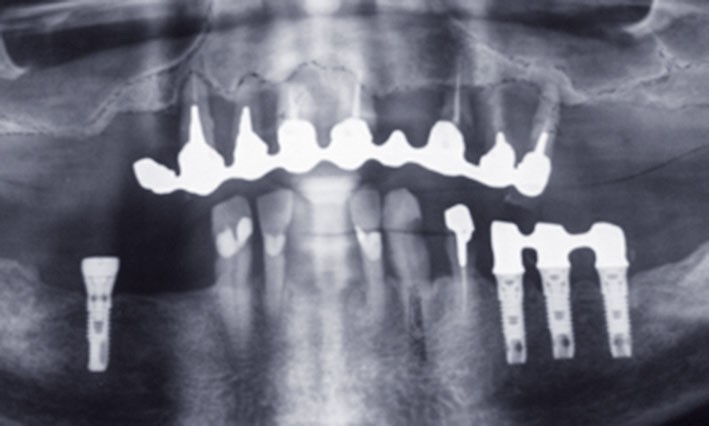

2) Devant l’urgence du problème, le traitement est initié au maxillaire. Le patient, ne désirant pas de chirurgie par comblement sous sinusien, six implants Cortex® (Co Mua) sont mis en place, dont un Saturn en position 21 et cinq Dynamix en situation 12, 14, 16 (angulé à 30°) et en situation 23 et 25 (angulé à 30°).

Des piliers multiunit Cortex® (Co Mua) sont vissés sur les implants, et l’ensemble est mis en charge immédiate par un bridge provisoire en résine acrylique renforcé au composite (fig. 3).